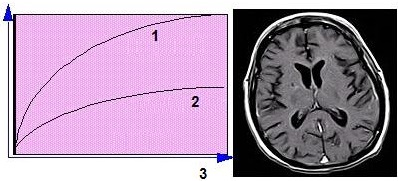

Each echo is used to create a different image, usually displaying different image contrast. The images below were acquired using a Spin Echo variable echo sequence. The first echo displays PD-weighting, while the second echo displays T2-weighting.

| Number | Description |

|---|---|

| 1 | First echo |

| 2 | Second echo |

T2 is the time constant that measures the transverse magnetization decay and spin-spin effects. Scan protocols that allow the T2 effects to predominate over the other contrast effects produce T2-weighted images. In T2-weighted images, tissues with short T2 are dark and tissues with long T2 are bright. In the brain, CSF produces the brightest signal on moderate to late TE images; pathology that alters and delays T2 also appear bright.

| 1 | Short T2 (fat) |

| 2 | Long T2 (water) |

| 3 | Time or TE period |